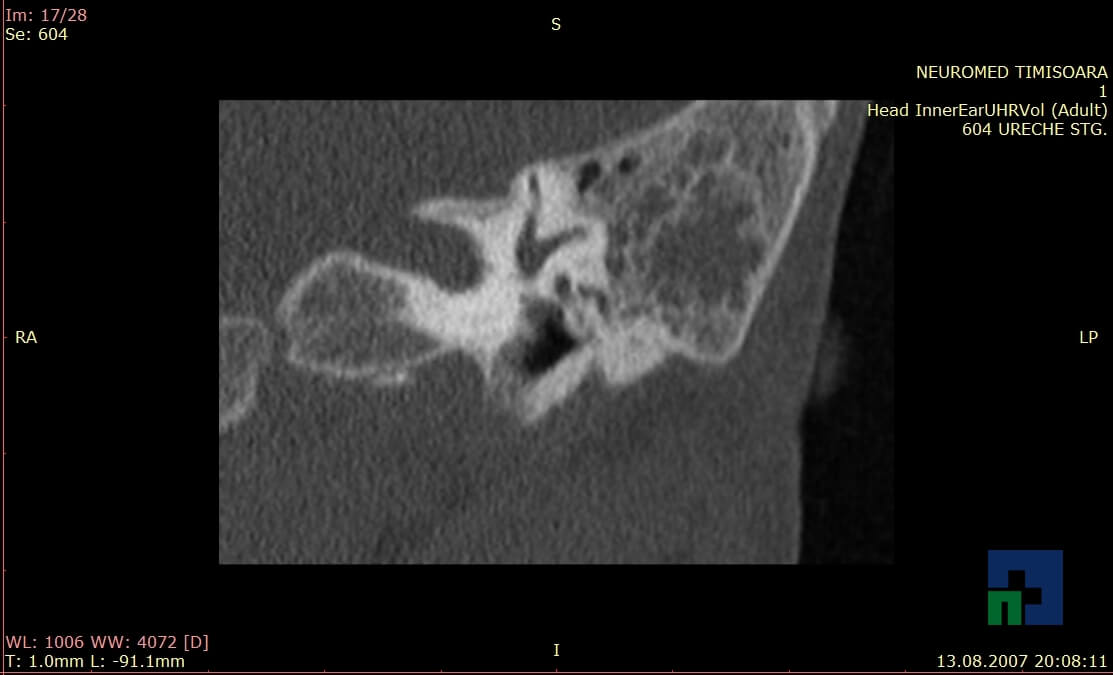

Examinare de rutină cerebrală, nativ și cu substanță de contrast (SDC) pentru diagnosticul:

- Diagnosticul traumatismelor de bază de craniu

- Diagnosticul fistulei LCR